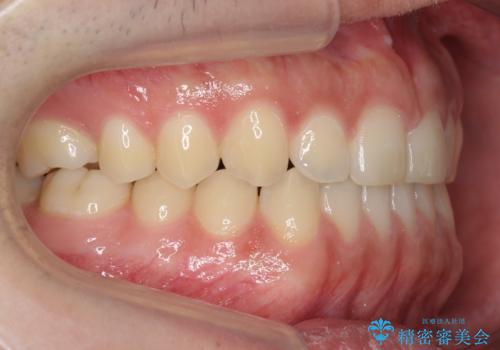

前歯のすきま 受け口 インビザラインで

- 前歯のすき間を気にして来院。

受け口もあり、前歯が端同士であたる、切端咬合となっていました。

下の歯のすき間を閉じて上の歯の内側に入るように位置付けました。

すき間もきれいに閉じ、満足していただきました。

上の前歯は下の歯と直接へりが当たっていた状態(切端咬合)だったため、形がいびつだったのは、わずかにやすりがけをして整えました。